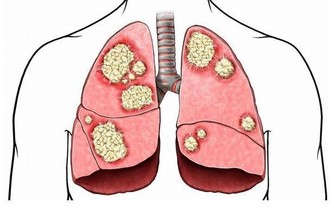

一方面,習慣性的便秘看似危害不大,但長期有毒物質存留於腸道中,會增加腸道腫瘤發生的風險;而另一方面,便秘又可能是腸癌的一個早期信號,這是因為腸道腫瘤的生長,阻礙了糞便的通過,所以才更有可能出現便秘的情況。

總之,排便這件事雖然是很多人不太看重的一件小事,但是和我們的腸道以及身體的整體健康關係密切,應該早點重視起來。排便越是有規律和暢通,患上腸癌的風險會越小。